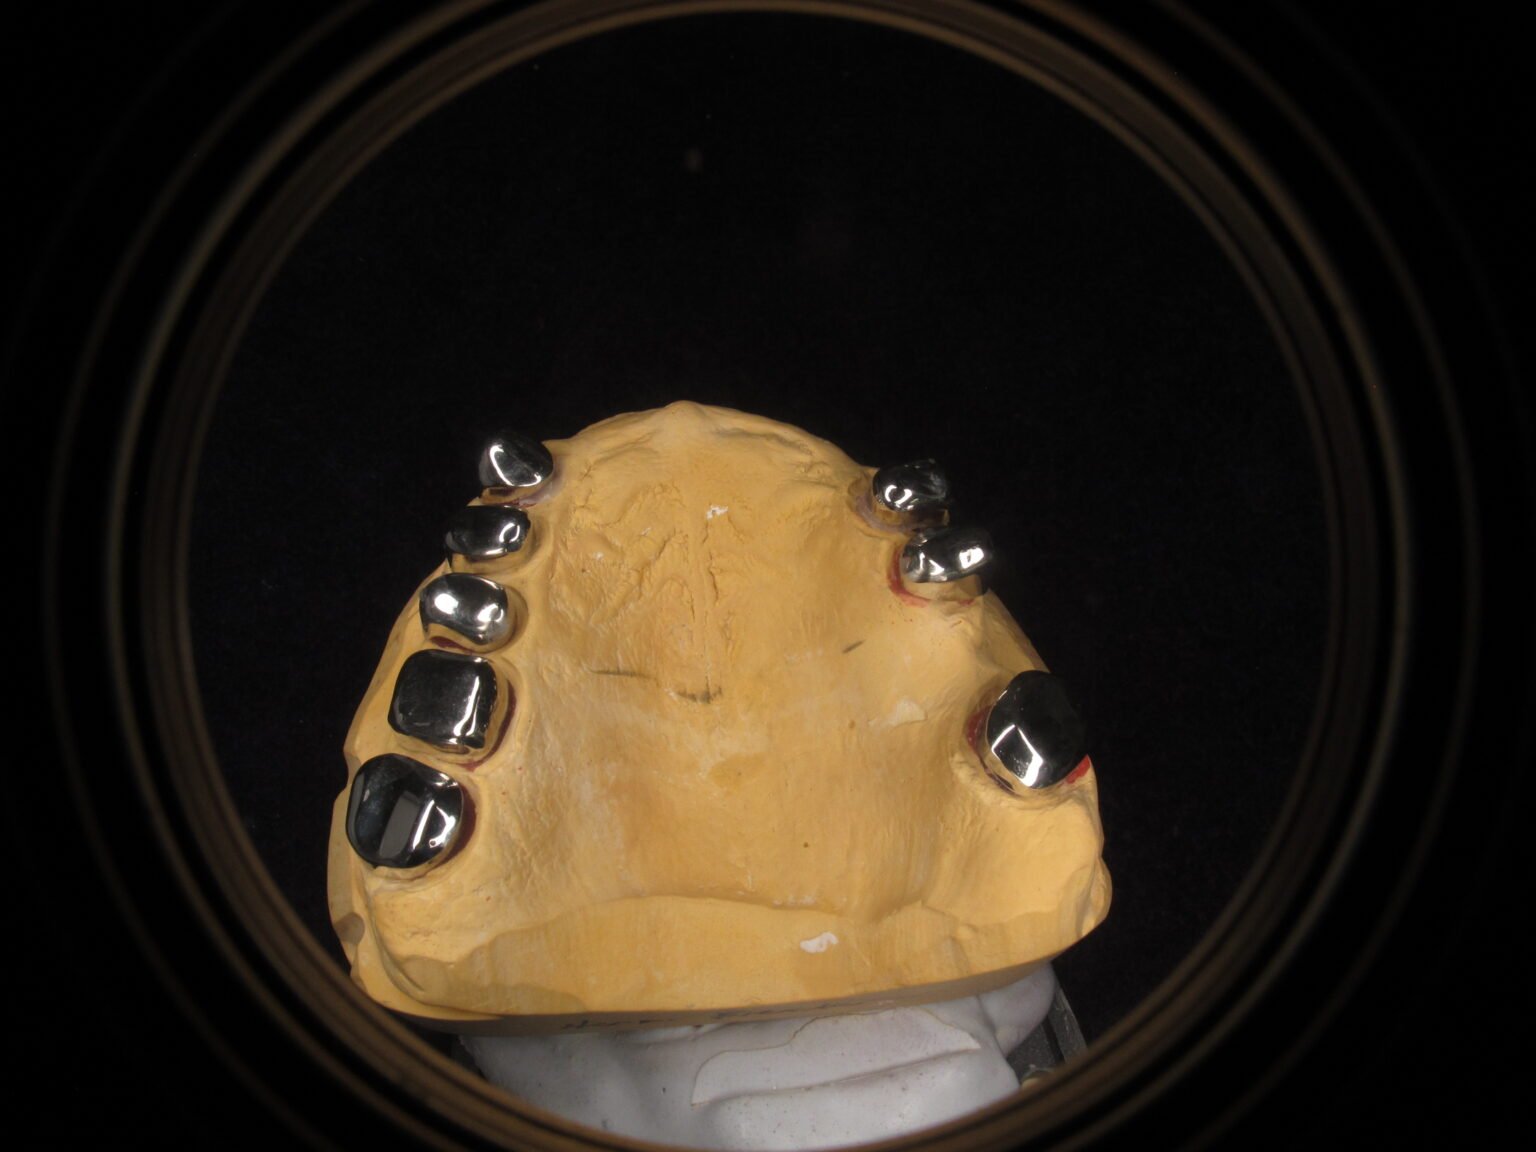

Teleskoparbeiten erfordern eine hochpräzise Fertigung, da Halt, Friktion und Einschubrichtung exakt aufeinander abgestimmt sein müssen. Unsere Primär- und Sekundärkronen entstehen vollständig im digitalen Workflow, sodass Parallelität, Wandstärken und Flächenqualitäten reproduzierbar eingehalten werden.

Die Primärkronen werden CAD/CAM-gestützt konstruiert und anschließend feinbearbeitet, wodurch definierte Friktionszonen und spannungsfreie Passungen sichergestellt werden. Die Sekundärteile werden darauf abgestimmt gefertigt, sodass das Ein- und Ausgliedern kontrolliert, weich und wiederholgenau funktioniert.

Für eine langlebige Funktionalität achten wir auf materialgerechte Gestaltung, exakte Okklusionsverhältnisse und eine harmonische Integration ins Gesamtkonzept des kombinierten Zahnersatzes.